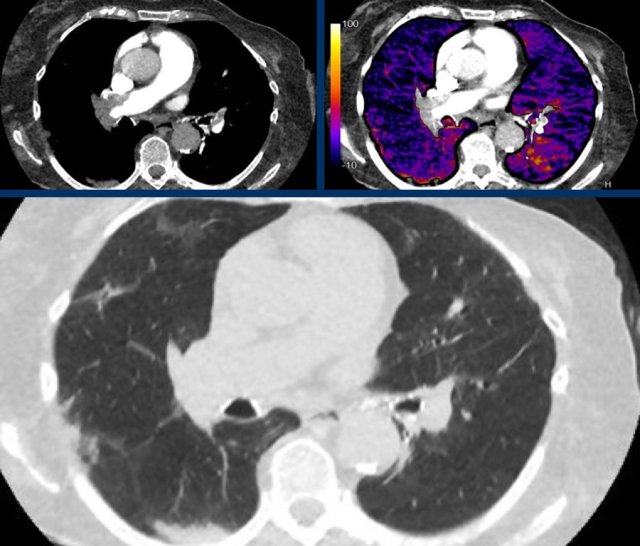

The images show:

- Central pulmonary embolism.

- Corresponding perfusion defects at subtraction iodine mapping.

- Peripheral, triangular pulmonary opacities in the vascular territories.